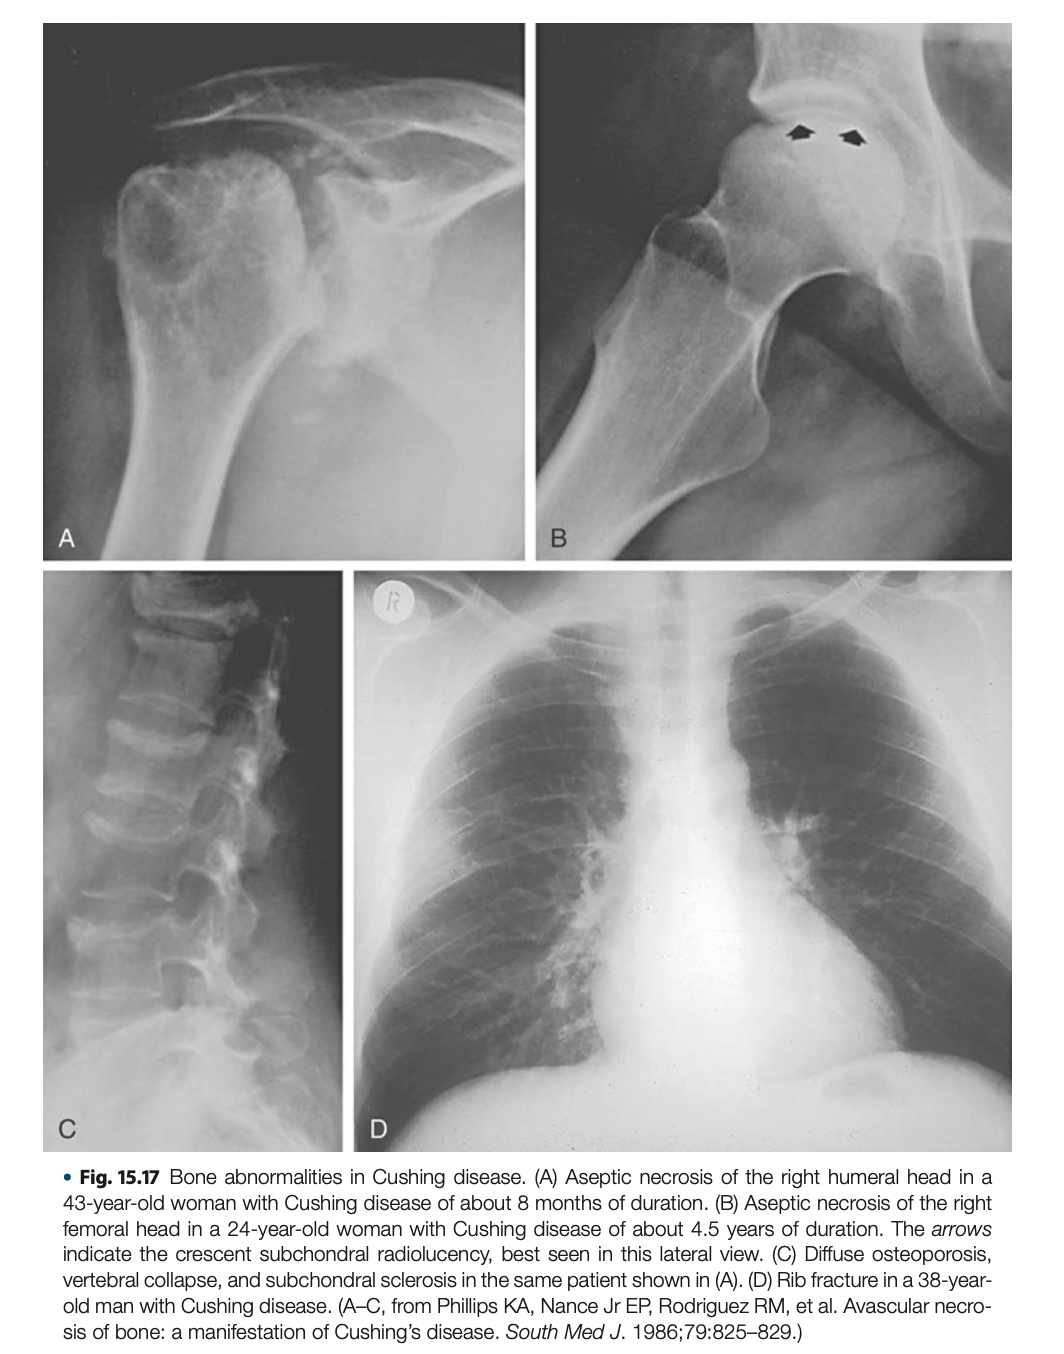

- 肌肉骨骼: 近端肌肉無力 (Proximal myopathy) (無法深蹲起立)、骨質疏鬆 (脊椎壓迫性骨折)、股骨頭缺血性壞死。